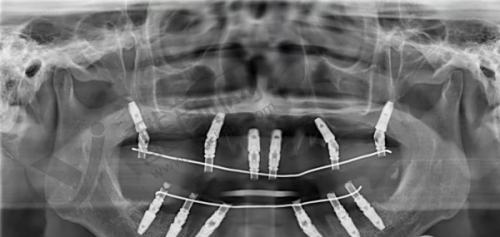

实例一:患者李先生,由于长期的牙齿缺失,导致咀嚼功能重度下降,面部也出现了一定程度的凹陷。陈丹军主事为他进行了详细的口腔检查和评估后,制定了all - on - 4即刻种植方案。在手术过程中,陈主事凭借不错的技术,顺利完成了种植体的植入。术后李先生修复良好,特别快就修复了正常的咀嚼功能,面部外观也得到了明显改善,整个人看起来年轻了许多。